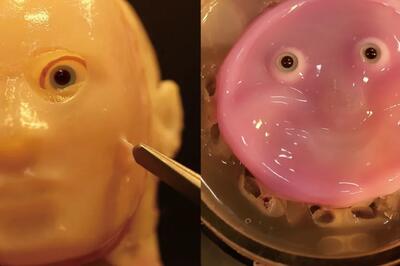

اندیشه معاصر - انقلاب در علم پزشکی/ احیای بینایی با استفاده از پیوند سلول های بنیادی برای نخستین بار در جهان اندیشه معاصر

دانشمندان ژاپنی توانستهاند با پیوند سلولهای بنیادی گرفته شده از سلولهای خونی انسان، بینایی را به افرادی که دچار آسیب قرنیه شدهاند، بازگردانند.